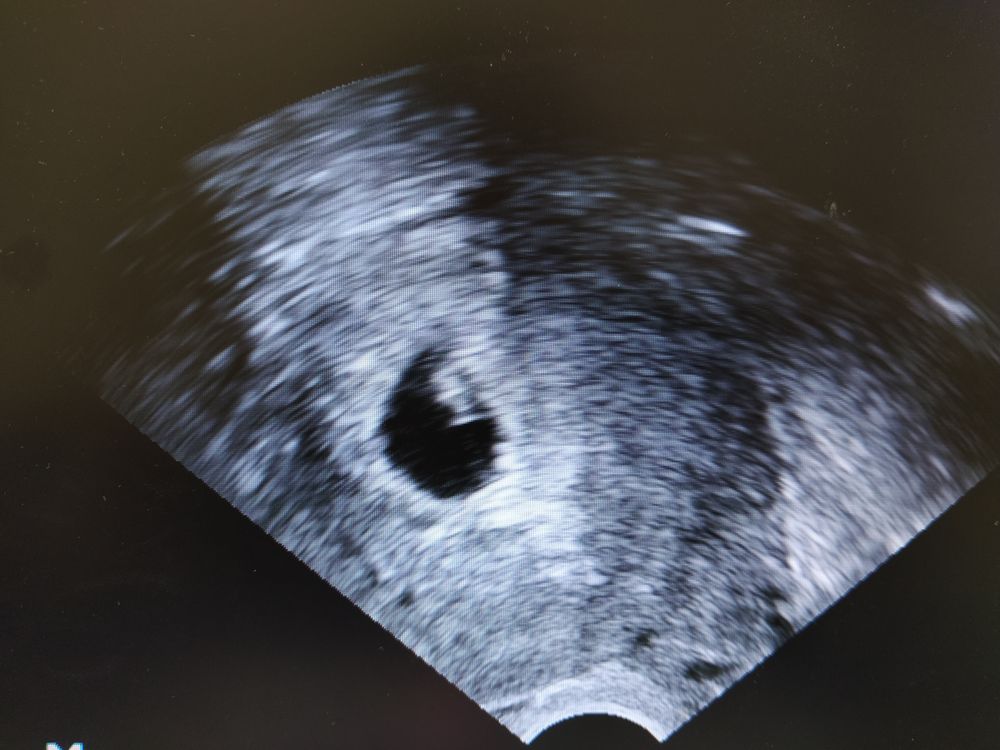

Сделала сразу в кабинете у себя УЗИ для подтверждения эмбриона и сердцебиения. Растет малышастик наш 😍 и сердечко видно мерцает. КТР сегодня 0,8см.